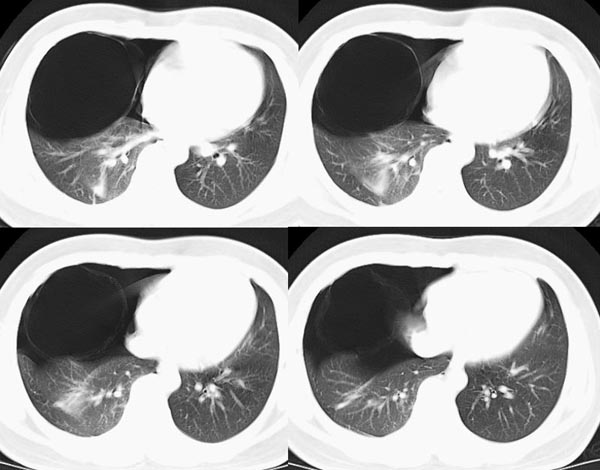

m21y既往体健,否认结核、支扩等病史;1周前患上感,无明显咳嗽,自觉无明显不适。单位体检透视时发现右侧液气胸!cr及ct如下(肺组织窗:l:-598hu w:1132hu):请大家会诊!!

右侧巨大含气囊性病变,壁薄、光整、其外侧见气体。右肺压迫性肺不张、胸腔内见少量积液。纵隔向左侧移位。左肺未见异常。诊断:1.右侧含气肺囊肿(先天性)。2.右侧液气胸。(少量液体)3.右肺压迫性肺不张。我也遇见一例这样的病人。女性。股骨外伤就诊。常规胸片发现右侧囊性病变。